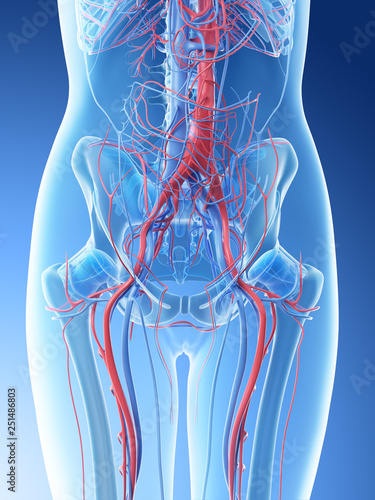

3d rendered illustration of a females abdominal vascular system